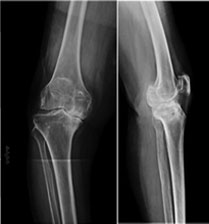

Joint Problems (Arthritis)

• Arthrolysis - Elbow